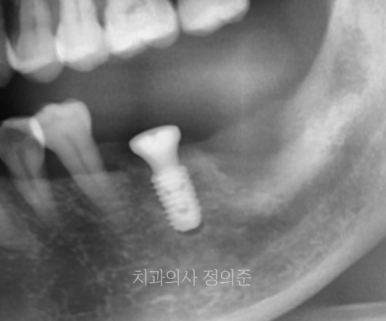

왼쪽 아래 첫번째 큰 어금니의 경우 큰 무리없이 임플란트 수술이 가능하여 1주일 정도 더 기다린 후에

임플란트 수술을 진행하였습니다. (우측 파노라마 사진)

기다리시는 동안 왼쪽도 식사가 가능하도록,

먼저 식립한 임플란트에는 임시보철물을 만들어 드렸습니다.

수술이 잘 마무리 되었고, 먼저 수술한 임플란트는 임시보철물로 식사가 가능하도록 하였습니다.

2023. 10